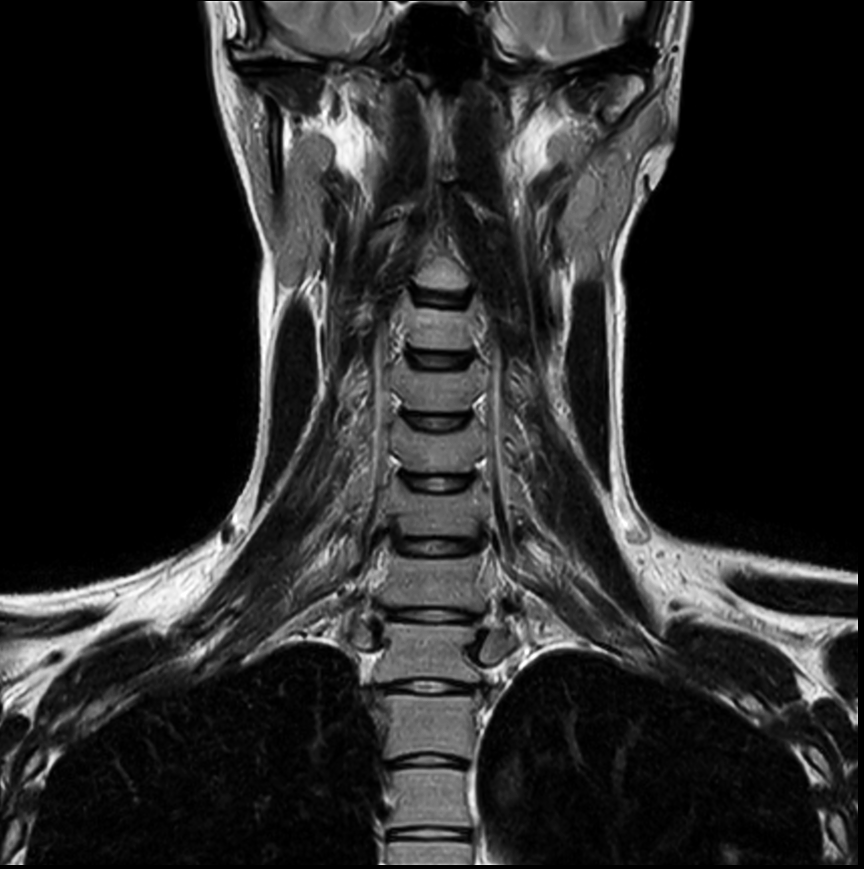

Coronal T2w TSE